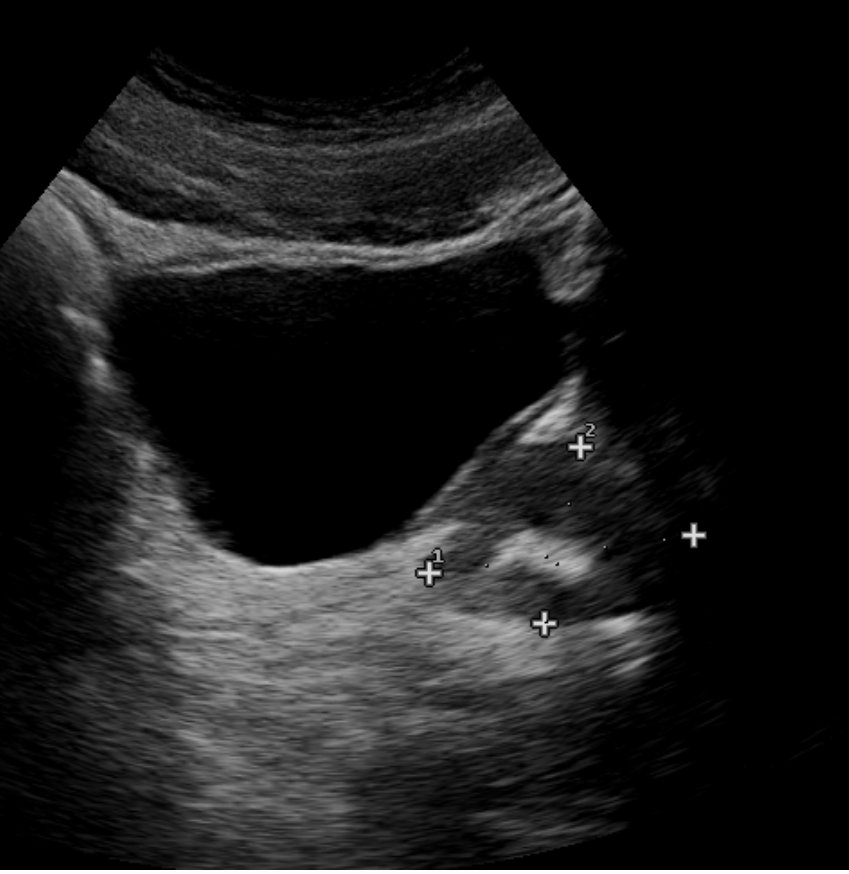

Find the normal lymph node

A normal lymph node is oval in shape and demonstrates a thin hypoechoic rim of tissue around an echogenic hilum. Abnormal lymph nodes demonstrate a more rounded shape, thickened cortex that can appear anechoic. and there is loss of differentiation of the hilum.